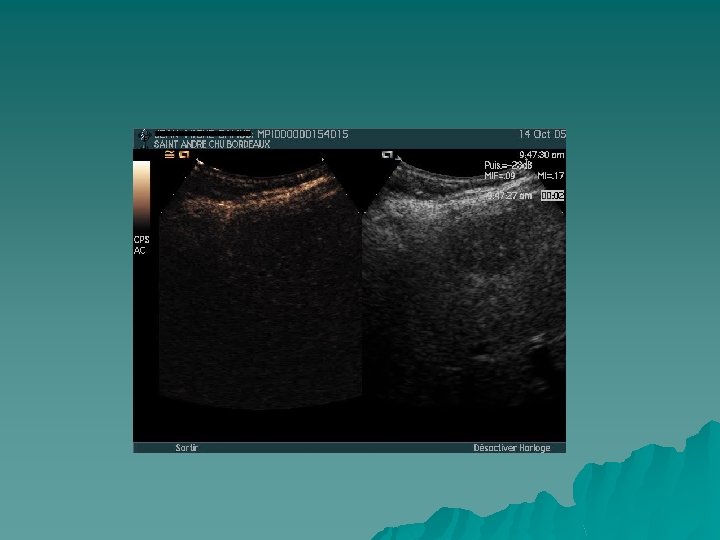

Monitorage des traitements percutanés u Aide à la visualisation du nodule u Évaluation traitement de l’efficacité du

PCUS phase tardive